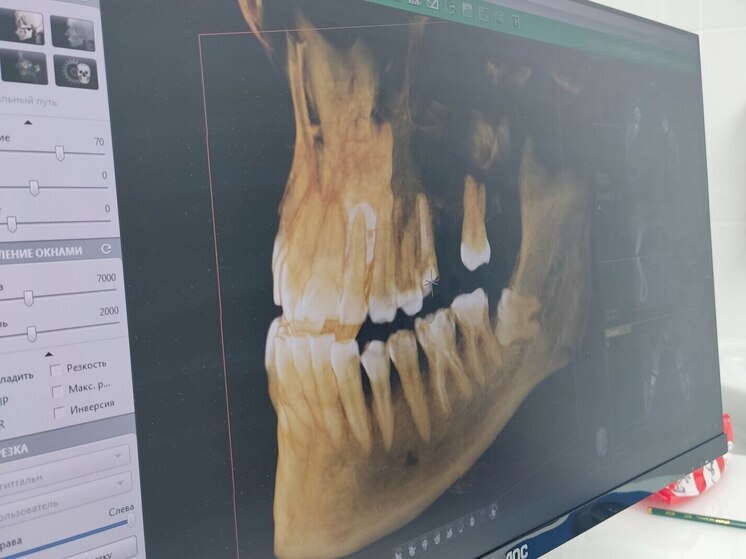

Специалист посоветовала людям с сахарным диабетом посещать стоматолога два раза в год. Фото: Архив МК в Великом Новгороде

Повышенный уровень глюкозы в крови создаёт благоприятную среду для развития инфекций и воспалений, а сухость во рту снижает защитные функции слюны, усложняя заживление повреждений. Об этом рассказала зубной врач Стоматологической поликлиники города Старая Русса Виктория Перминова, пишет пресс-служба Минздрава региона.

Специалист посоветовала людям с сахарным диабетом посещать стоматолога два раза в год, делать глубокую чистку зубов каждые полгода, чтобы удалить налет и камень. Не менее важно соблюдать определенную диету и избегать продуктов с сахаром, которые приводят к кариесу.